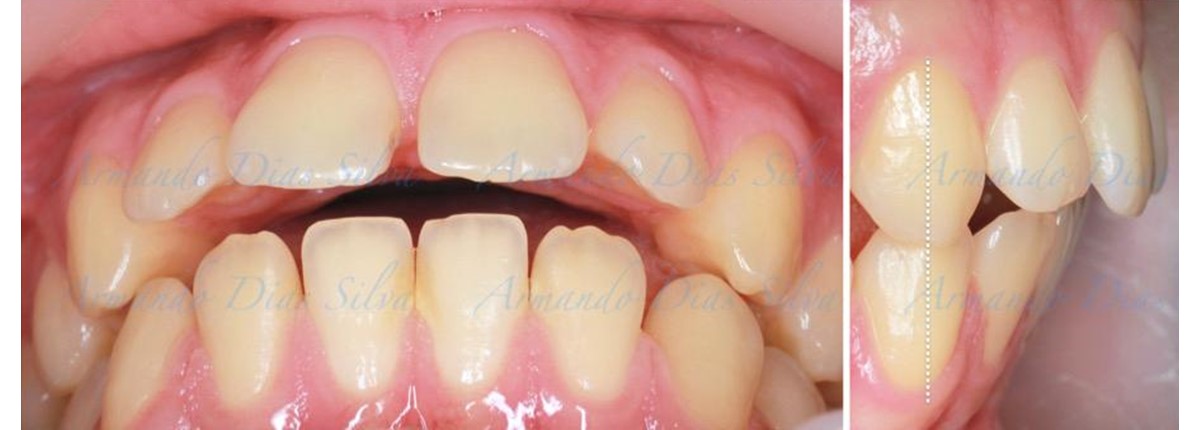

Clase II, Div. 1: Protrusión del incisivo central y espacios anteriores (SureSmile® Aligners)

Principal queja del paciente: Protrusión del incisivo central y mordida abierta. El paciente rechaza la expansión del arco palatino (MARPE) y las extracciones.

Este paciente adolescente presenta molares de Clase II y no le gusta su mordida abierta ni lo protrusivos que son sus dientes frontales. Por sus fotografías faciales, parece que su mandíbula es retrognática o le falta volumen en la barbilla. El historial del paciente también indica que existe un problema funcional al no haber guía de los incisivos.

• Molares de clase II

• Diastema

• Espaciamiento leve de las arcadas superior e inferior (deficiencia transversal de 3,45 mm)

• El primer molar superior derecho está en una posición más mesial que el primer molar superior izquierdo

• Deficiencia transversal maxilar leve (3,45 mm)

• Incisivos superiores e inferiores proclinados

• Orientación canina desfavorable